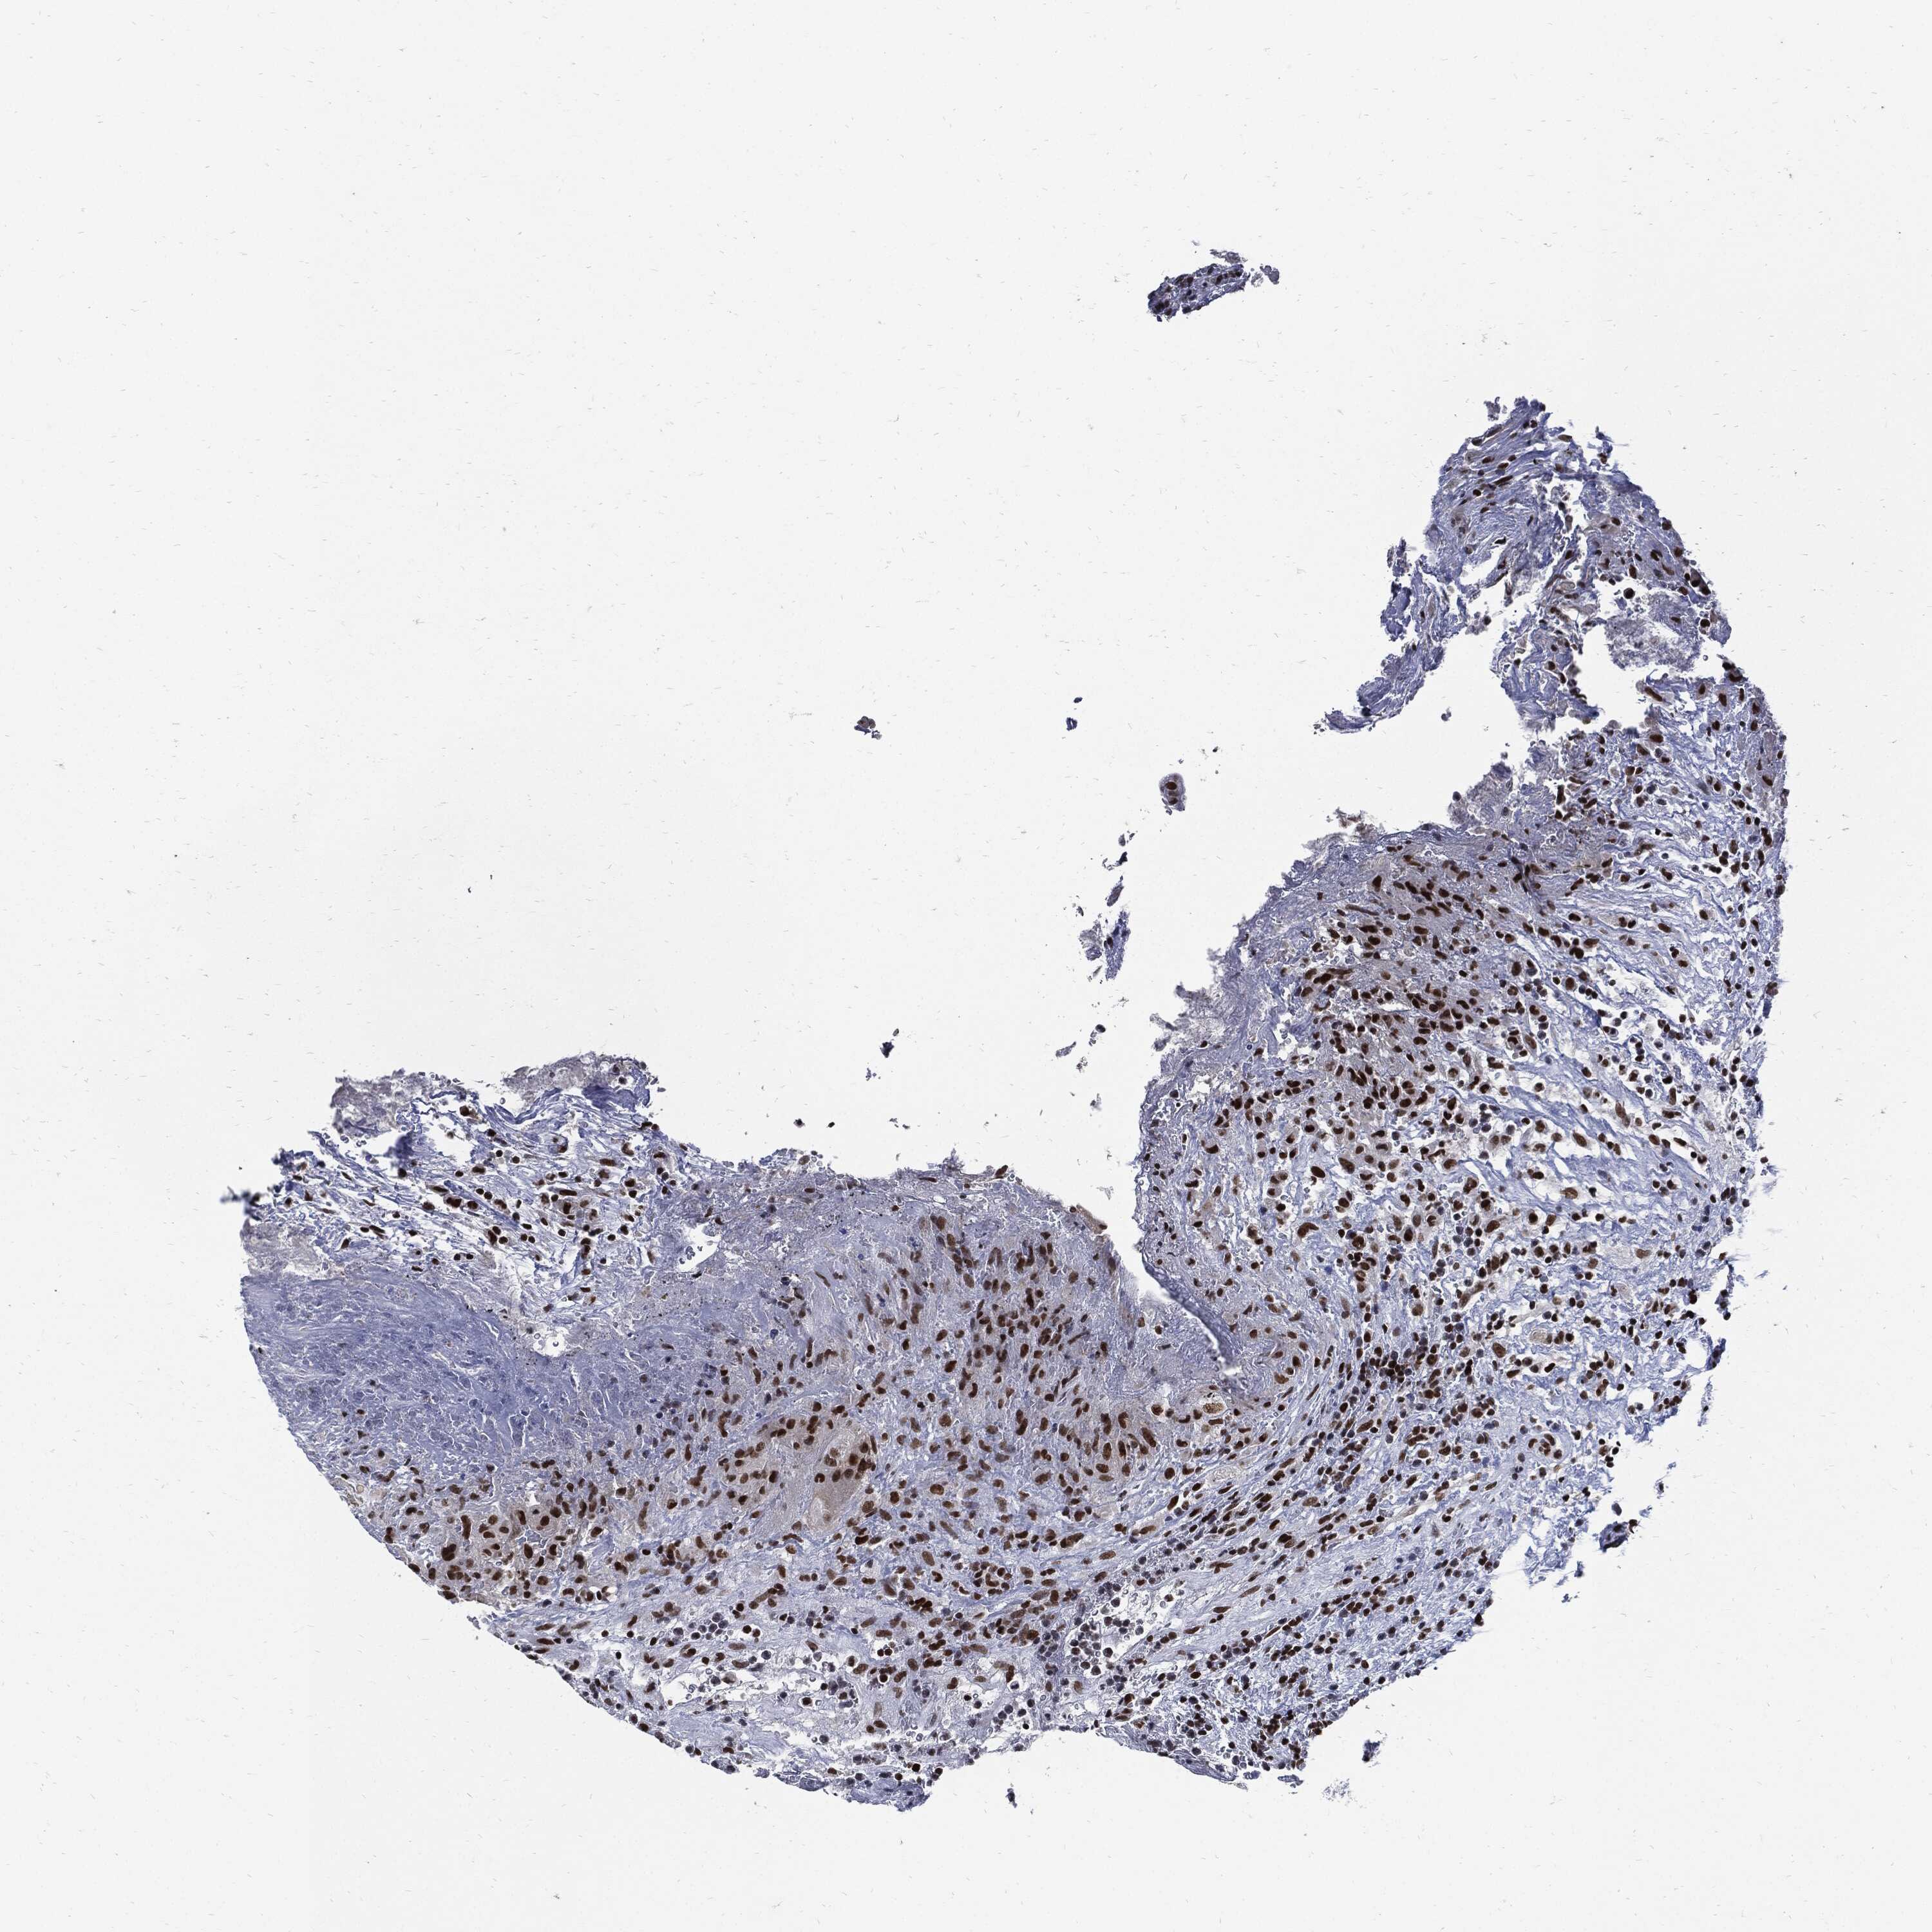

UROTHELIAL CANCER - Protein expressioni

A mouse-over function shows sample information and annotation data. Click on an image to view it in a full screen mode. Samples can be filtered based on level of antibody staining by selecting one or several of the following categories: high, medium, low and not detected. The assay and annotation is described here.

Note that samples used for immunohistochemistry by the Human Protein Atlas do not correspond to samples in the TCGA dataset.

Antibody stainingi

Antibody staining in the annotated cell types in the current human tissue is reported as not detected, low, medium, or high, based on conventional immunohistochemistry profiling in selected tissues. This score is based on the combination of the staining intensity and fraction of stained cells.

Each image is clickable and will lead to virtual microscopy that enables deeper exploration of all samples and also displays staining intensity scores, fraction scores and subcellular localization as well as patient and tissue information for each sample.

Antibody HPA001907

Antibody HPA002735

Antibody CAB010451

Antibody CAB080271

Location

Nuclear

Cytoplasmic/membranous

Cytoplasmic/membranous,nuclear

None

Urothelial carcinoma, High grade

Urothelial carcinoma, Low grade